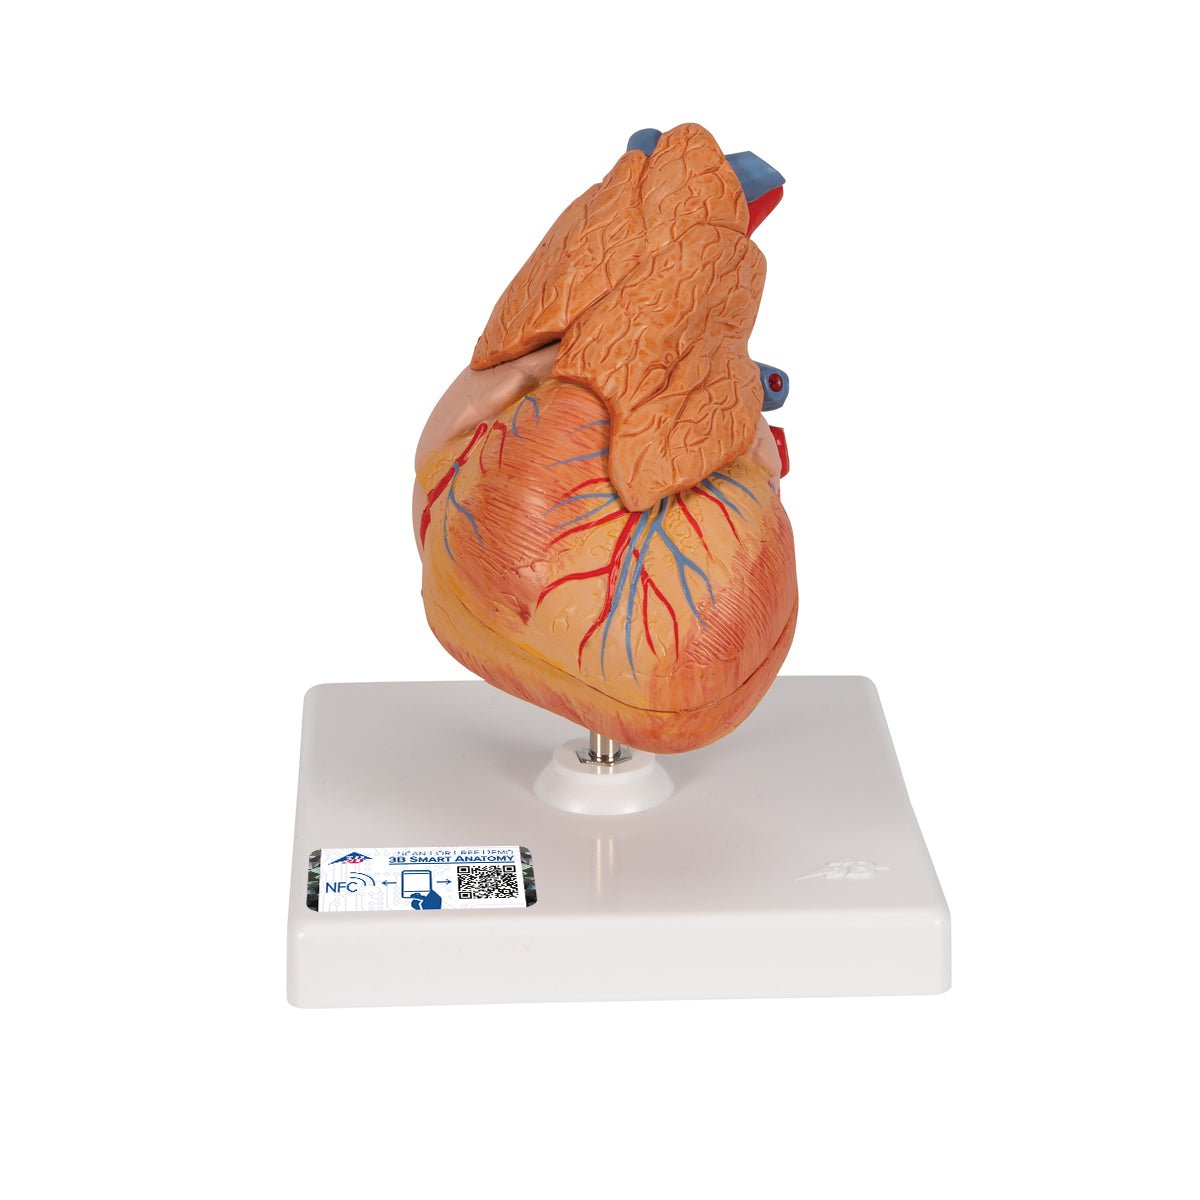

Anatomical models

Selling anatomical models is the mainstay of eAnatomi, although we also spend a lot of resources developing our own anatomical materials such as posters. Anatomical models are used for various purposes and can show both defined tissues, organs and organ systems. Are you looking for a simple model of bone tissue or perhaps an advanced torso model based on MRI technology, you can find it all at eanatomi.com.